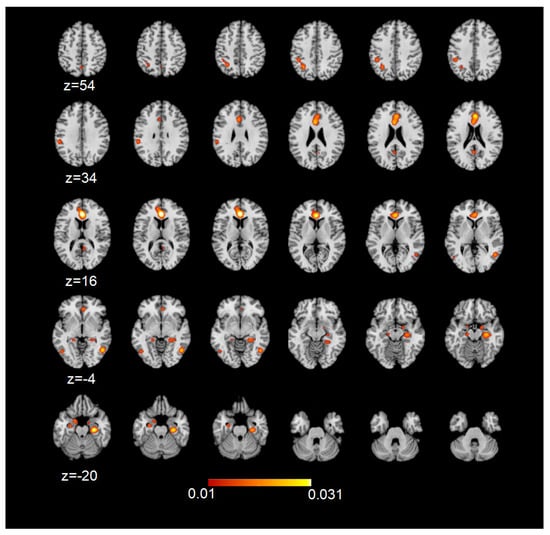

| Cluster | BA | Hemisphere | x | y | z | ALE | p | Z |

|---|---|---|---|---|---|---|---|---|

| Anterior cingulate cortex | 24 | L | 0 | 34 | 14 | 0.04148 | 0.00000 | 9.389 |

| Middle temporal gyrus | 21 | R | 50 | −60 | 0 | 0.02803 | 0.00000 | 7.215 |

| Posterior cingulate cortex | 23 | L | −2 | −54 | 22 | 0.01799 | 0.00000 | 5.306 |

| Parahippocampal gyrus | -- | L | −30 | −8 | −22 | 0.01898 | 0.00000 | 5.510 |

| Parahippocampal gyrus | -- | L | −22 | −36 | −4 | 0.01617 | 0.00000 | 4.917 |

| Posterior cingulate cortex | 31 | R | 6 | −56 | 26 | 0.01382 | 0.00001 | 4.390 |